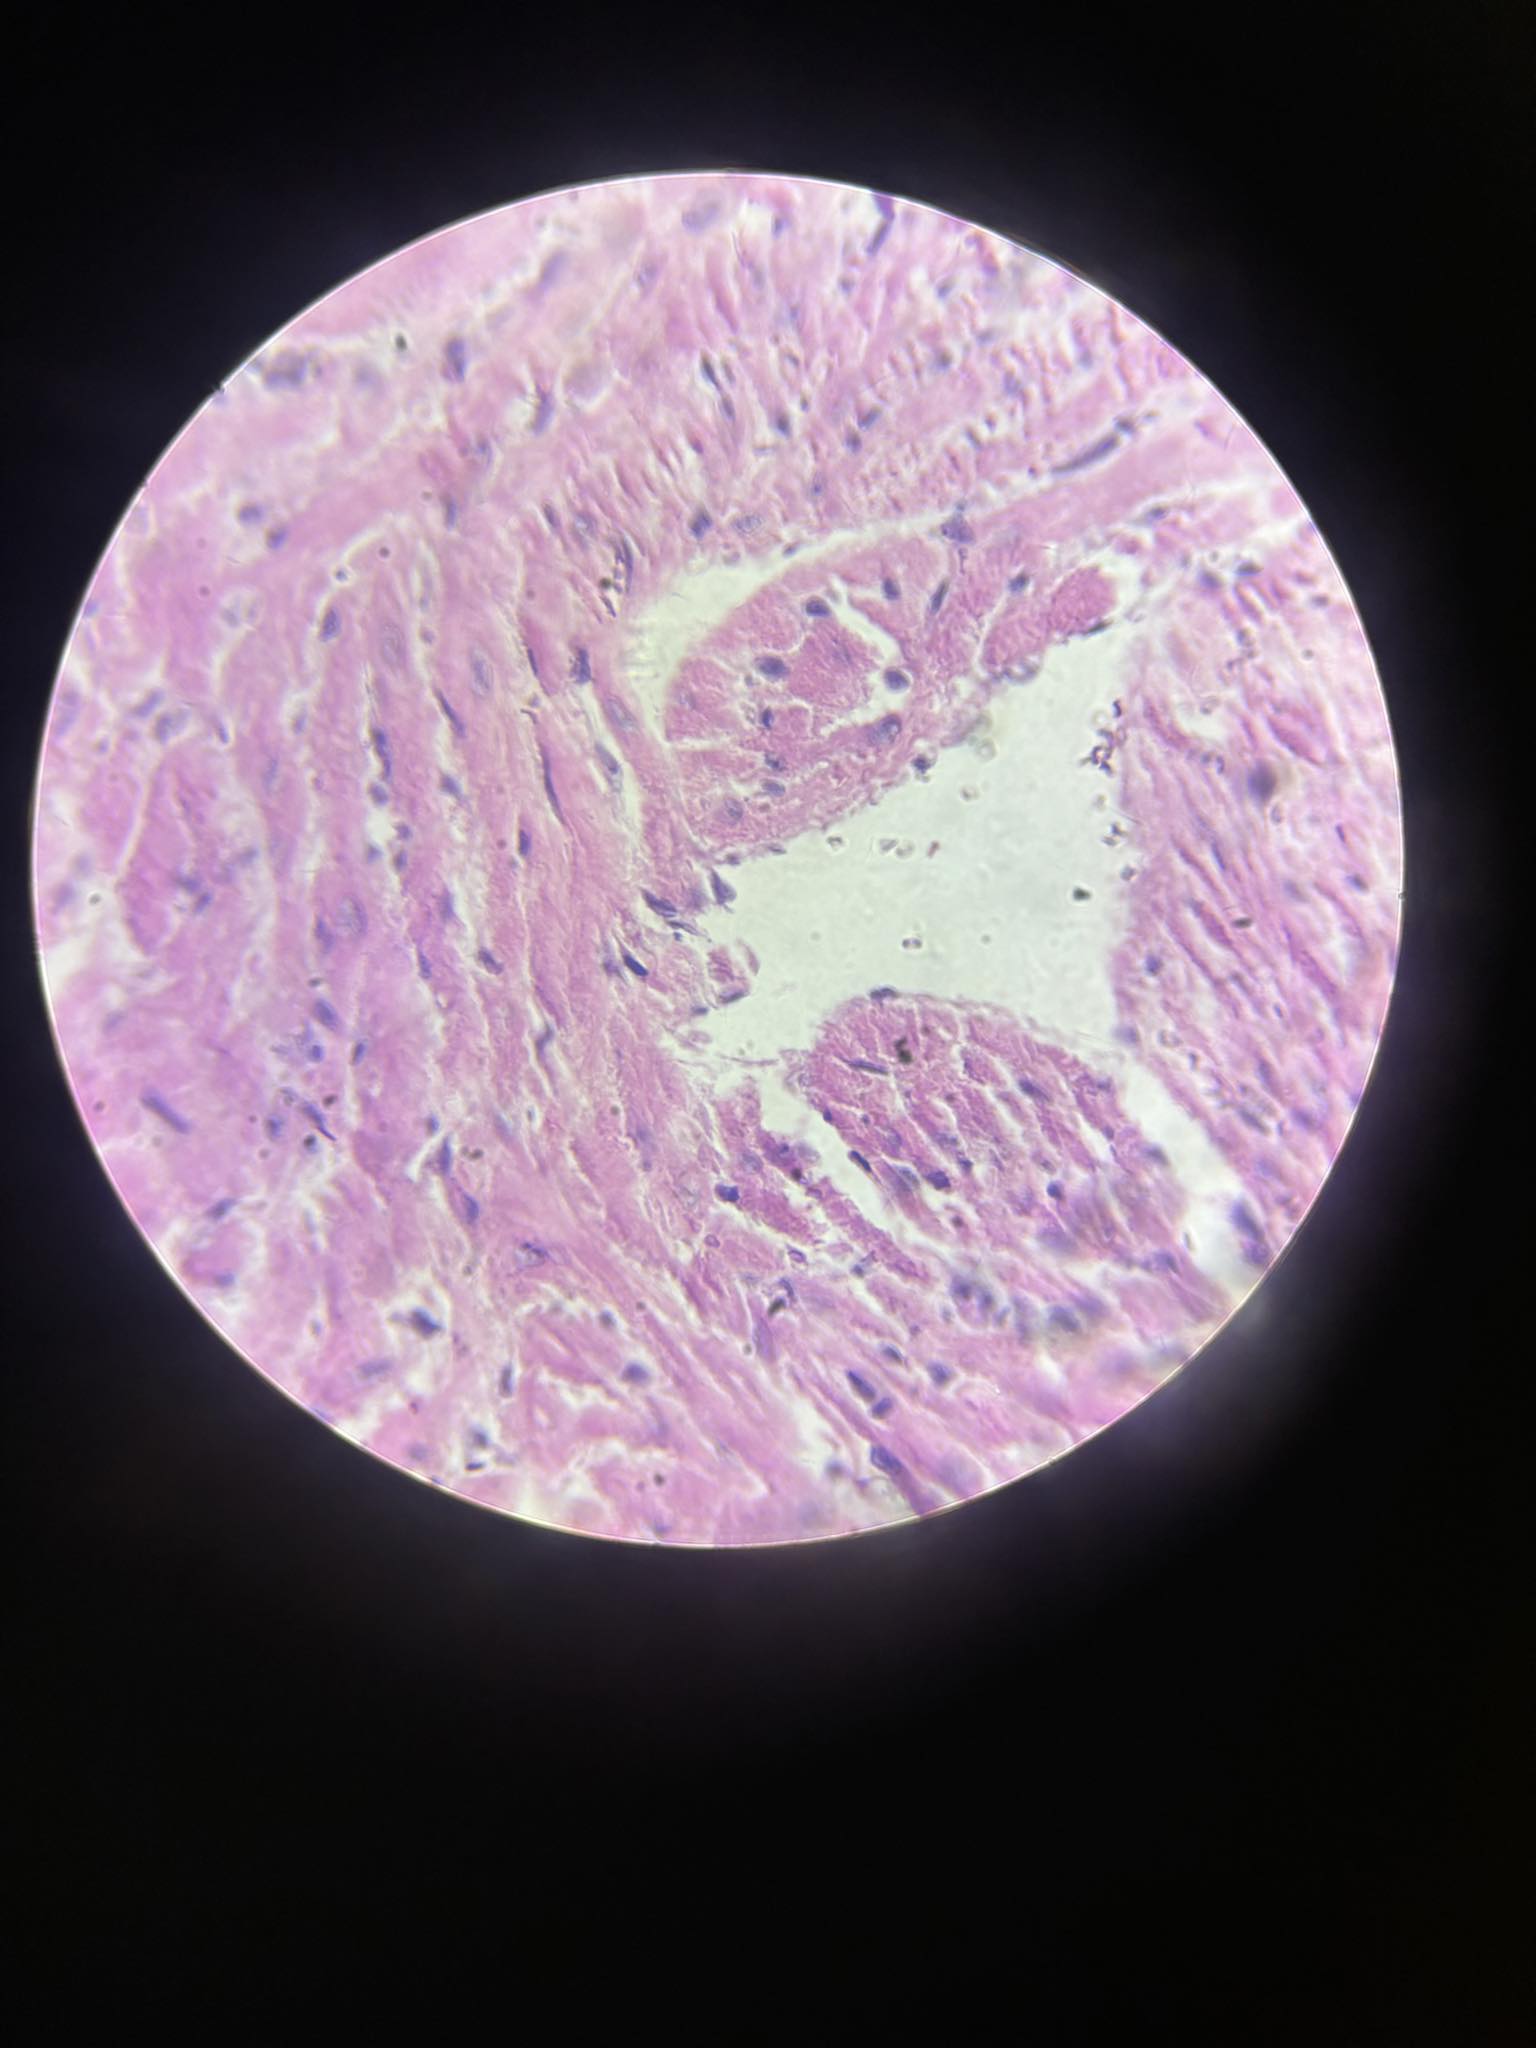

trichinella spiralis larwy otorbione